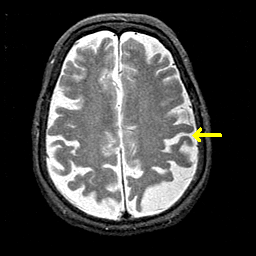

Alzheimer's disease MR T2-weighted -- Slice #33

Tour 2: Next/Previous/Start: Find the central sulcus. To get properly oriented, view the MPEG movie ("cine" button, next to the sagittal image) of the entire dataset, and find the central sulcus by first locating the marginal sulcus in the medial parietal lobe. From the marginal sulcus, the central is usually the first encountered when moving anteriorly. Compare this with the functional image at the same level (use the buttons at right, or choose the SPECT-Tc tickmark on the timeline). Note that both pre- and post- central gyri, where the primary sensori-motor cortices are located, are relatively hyperperfused. In general, Alzheimer's disease is associated with reduced brain function, especially in non-primary regions. The association cortex of the parietal lobes is often severely affected, as illustrated in this case.

[Home][Help][Clinical][Tour 1][Tour 2] Slice 33